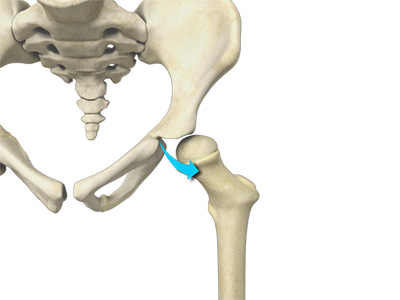

Hip Movements

All of the anatomical parts of the hip work together to enable various hip movements. Hip movements include flexion, extension, abduction, adduction, circumduction, and hip rotation.